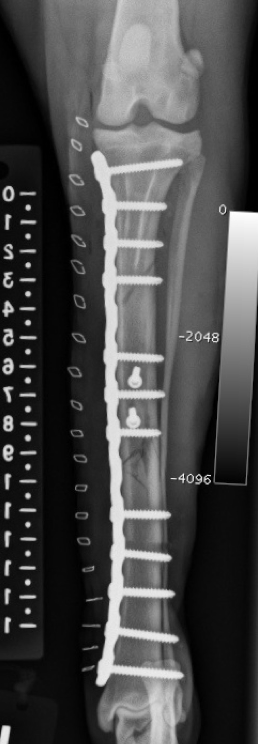

This large segmental tibia-fibula fracture in an Irish Wolfhound was managed by interfragmentary screws and a large medial bone plate applied in a neutralization fashion.